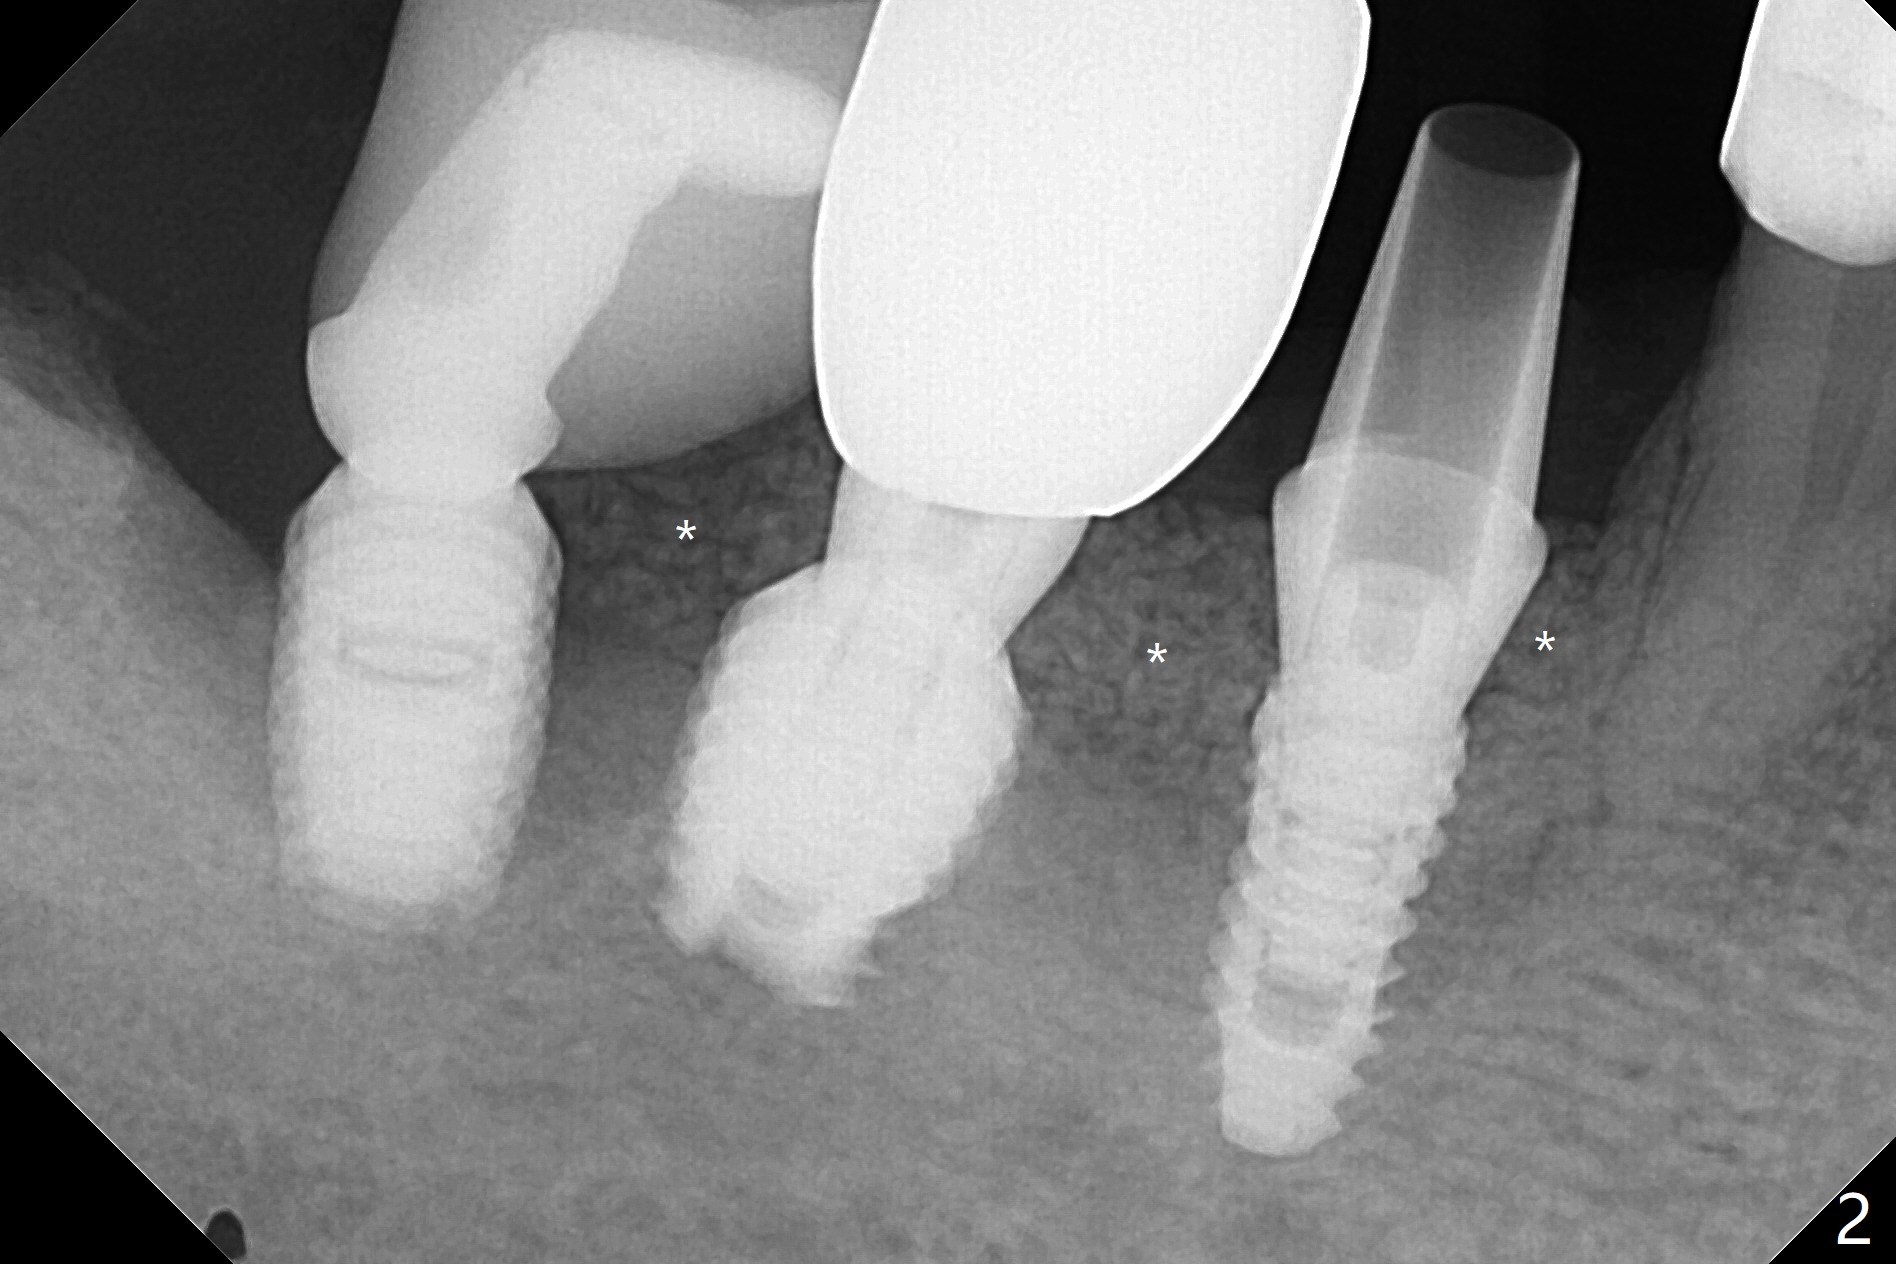

28牙位3.5x8.5毫米植体导板植入后,颊侧远中螺纹暴露,为了植骨,附近骨壁钻洞创造出血点以及放置基台(图一:5x7.5(3)毫米)。放置粘性骨粉后(图二:*),覆盖薄层PRF,后者可能很快吸收,为了防止骨粉暴露,放置不可吸收膜(图三:*),当中打洞,穿过基台固定,表面缝合。术后六周不可吸收膜部分暴露(图四)。图五,六显示在取出时膜当中固定用的洞,下面伤口愈合正常(图七)。